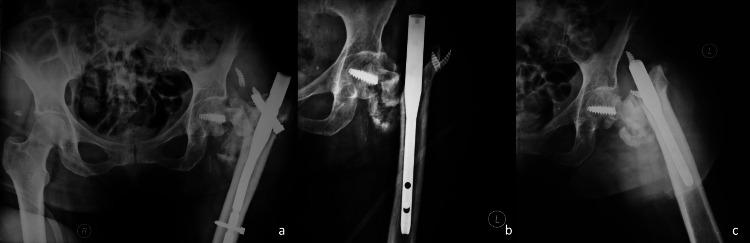

Intramedullary nailing is an established method for treating pertrochanteric fractures. However, the widespread use of this technique comes along with a variety of complications. We present a case of a 50-year-old female who presented to the emergency department suffering a left pertrochanteric fracture. She was treated with proximal femoral nailing and discharged home. Nine months later, she presented again to the emergency department with pain and an inability to bear weight. Imaging revealed the mechanical failure of the hip screw and loss of fracture fixation. Revision surgery included extraction of the broken hardware and a left hip hemiarthroplasty. The removed implant was sent for further evaluation. Fractographic analysis showed acute breakage due to bending and torsion forces acting on the screw with no relevant signs of metal fatigue. This biomechanical method is of great value for the surgeon and the implant manufacturer in order to understand the failure pattern and optimize future implants and fixation techniques. Improved implant biomechanical properties together with meticulous surgical technique constitute the cornerstones for optimal results.

髓内钉固定术是治疗转子间骨折的一种成熟方法。然而,这项技术的广泛应用伴随着各种并发症。我们报告一例50岁女性,因左侧转子间骨折就诊于急诊科。她接受了股骨近端钉固定治疗后出院回家。九个月后,她再次因疼痛和无法负重就诊于急诊科。影像学检查显示髋螺钉出现机械故障,骨折固定失效。翻修手术包括取出断裂的内固定器械并进行左侧髋关节半关节置换术。取出的植入物送去做进一步评估。断口分析显示,螺钉因弯曲和扭转力导致急性断裂,无明显金属疲劳迹象。这种生物力学方法对于外科医生和植入物制造商理解失效模式以及优化未来的植入物和固定技术具有重要价值。改善植入物的生物力学性能并辅以细致的手术技术是取得最佳效果的基石。